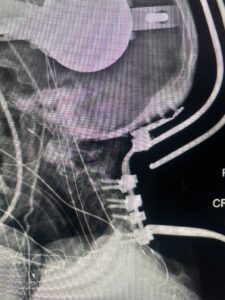

Cervical x-rays revealed a significantly increased atlanto-axial interval (Fig. 5) On review of her imaging studies it was noted that the right C2 isthmus was very thinned by the vertebral foramen (Figs 6a, b, and c) which would make an attempt at placing a C2 pars screw dangerous. A decision was made to perform an occipital-cervical fusion because only possible unilateral fixation and an extensive C1 laminectomy to be performed eliminating a fixation point if a more traditional C1-C2 was performed. Even if C1 lateral mass screws were able to be placed one could only perform a unilateral screw construct fixation to C2. We performed an occipital cervical fusion down to C4 to get enough inferior fixation and C1 laminectomy. The decompression went well. We placed a left unilateral pars screw and bilateral C3 and C4 lateral mass screws. We placed three 12 mm screws in the midline keel (Fig. 7). Postoperatively the patient had all around improvement in her symptoms and did not qualify for rehab. Her post op films at 6 weeks (Fig. 8)

Fig. 7: Intraoperative photograph demonstrating occipital-cervical construct and C1 laminectomy (blue dot). Note the 3 screws in the midline keel (blue arrow)

Fig. 8: Intraoperative photograph demonstrating occipital-cervical construct and C1 laminectomy (blue dot). Note the 3 screws in the midline keel (blue arrow)